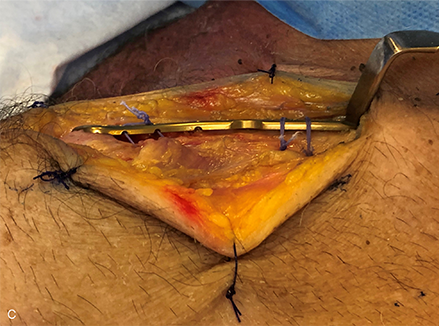

Figure 1a–c Distal clavicular fixation during prototype evaluation of the novel VA Clavicle System. Lateral is to the left in all figures. Conformation of the plate to the superior topography of the distal clavicle is designed to facilitate positioning of the distal margin of the plate parallel to the acromioclavicular joint (a) and respects the almost universal 12o downward tilt of the distal clavicle in the lateral fifth of the bone (b), while also allowing the plate to follow the beginning of the twist region at the junction of the second and third fifths of the bone (c).